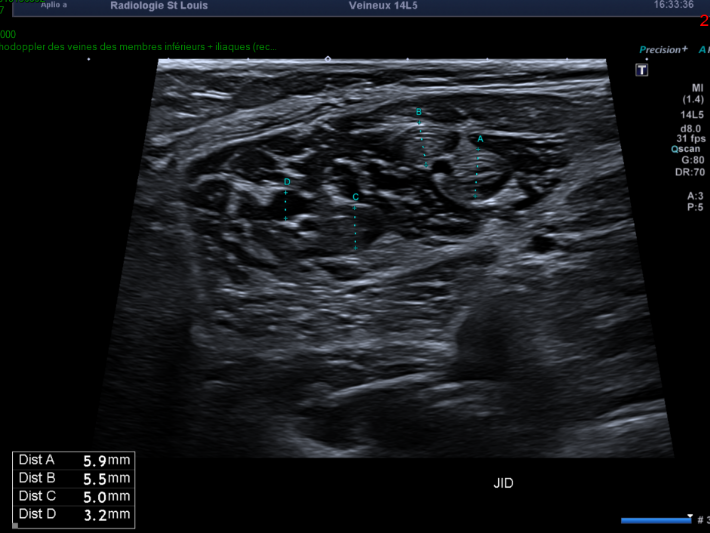

Veines gastrocnémiennes médiales droites.

Les veines gastrocnémiennes médiales droites sont incompressibles, dilatées, sièges d’un thrombus s’étendant sur toute leur hauteur, sans extension à la veine poplitée.

Devant l’absence d’incompressibilité de ces veines sur l’examen antérieur, on évoque une thrombose veineuse récente qui est une complication de l’immobilisation en rapport avec la douleur musculaire.

Il s’agit d’une complication classique qu’on retrouve dans les lésions musculaires, il faut donc toujours penser à la rechercher.